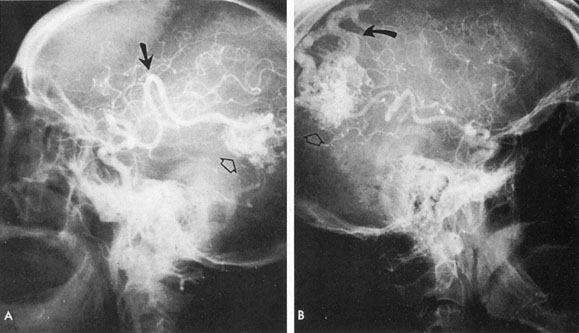

From 85% to 90% of AVMs are in the supratentorial compartment and are supplied primarily by the carotid circulation (Figs. 7 and 8). The remainder are supplied by the vertebrobasilar system. The approximate frequency of location is as follows: frontal, 22%; temporal, 18%; parietal, 27%; occipital, 5%; and deep intraventricular or paraventricular, 18%. The intracerebral site of the malformation does not necessarily indicate that there will be signs referable to that area simply from the mass effect of the malformation. Clinical features primarily result from subarachnoid hemorrhage or intraparenchymal hemorrhage with hematoma formation.

Fig. 7. Supratentorial arteriovenous malformation in a 28-year-old woman with a history of focal motor seizures for many years and a recent subarachnoid hemorrhage. A: Lateral projection carotid arteriogram demonstrating a huge deep hemispheral arteriovenous malformation. B: Frontal projection. C: Fundus photograph showing anomalous tortuous vasculature in each eye. No retinal arteriovenous shunt was detectable.

Fig. 8. Multiple supratentorial arteriovenous malformations (AVMs). A: Lateral projection of left carotid arteriogram shows dilated afferent artery (solid arrow) feeding the right hemispheric parietal AVM (open arrow). B: Right carotid injection fills a second, more posteriorly located, parietooccipital AVM (open arrow), which drains immediately to markedly dilated cortical veins (curved arrow).